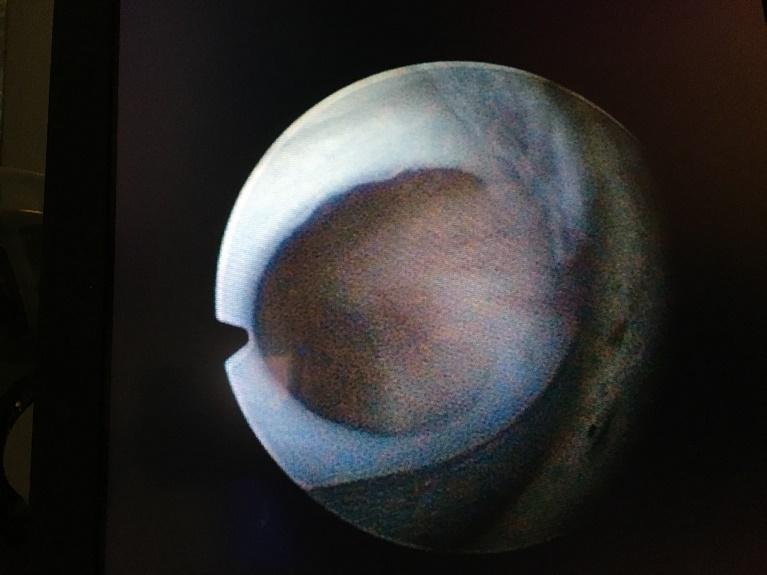

20 weken echografie: links: dikwandige blaas met verwijding van de plasbuis tot aan de kleppen (pijl): het “sleutelgat teken”. Onder: verwijde urineleiders. Bij kinderen gaan de urineleiders bij verwijding ook erg gekronkeld verlopen.

Verwijde nierbekkens (lange pijl) en nierkelkjes (korte pijl). Smalle nierschors.